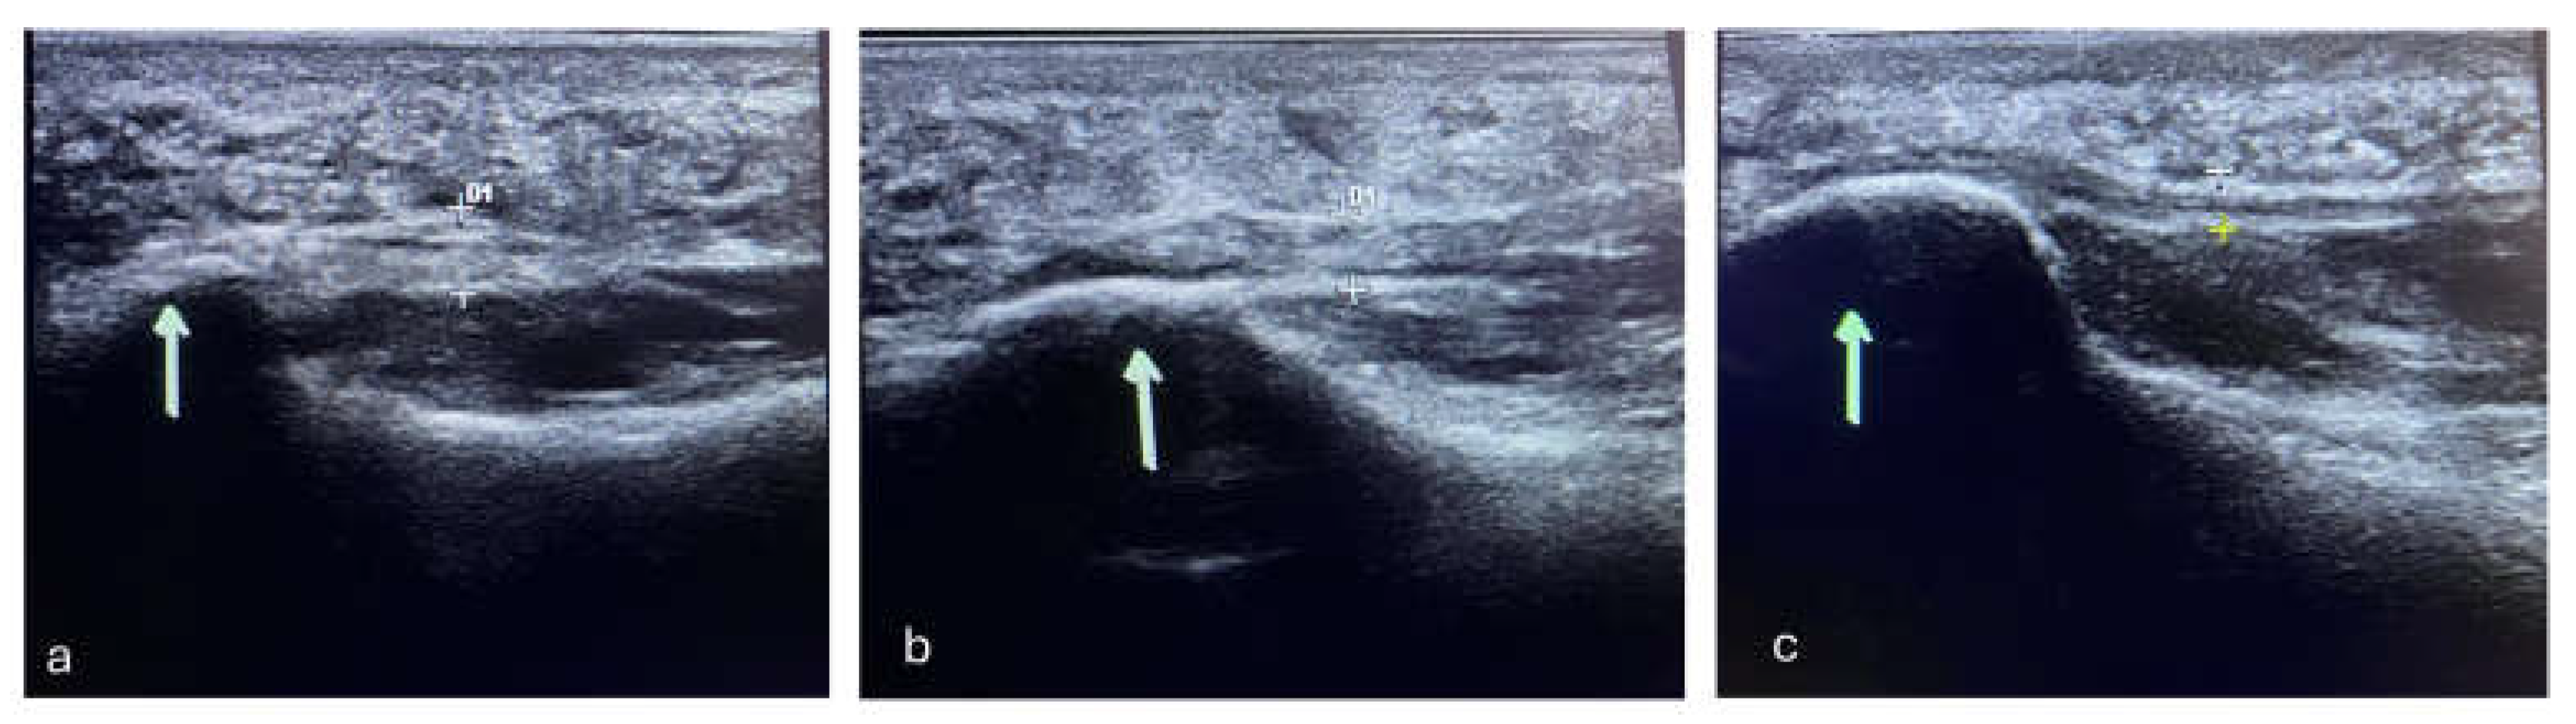

The mean RM score at T1 was 1.96 (±0.88), while it dropped to 1.68 (±0.89) at T2. When measured via echography, the fascia plantaris of enrolled subjects had a mean thickness reduction of -0.57mm (±0.74mm) between T0 and T2; this reduction was significant for both the laser group (t: 4.67; p-value <0.001) and the control group (t: 2.85; p-value: 0.005) (Figure 2). Finally, 12.77% of patients (6/47) showed MRI bone edema remission over time (Figure 3). No adverse effects were recorded in the two groups. The VAS, FFI and RM score changes over time are described in Table 3.

Figure 2. Ultrasound of the plantar fascia of a patient suffering from plantar fasciitis belonging to the laser group. At T0 there was a band thickness of 5 mm, which reduced to 4 mm at T1 and T2 to 3 mm.